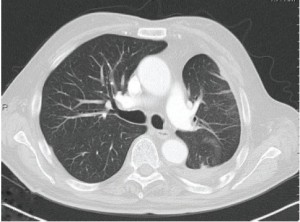

This is a 79-year old man with previous occupational asbestos exposure presenting with unilateral left-sided pleural effusion. Initial CT-scan showed a thickened pleura within the left chest (Figure 1). After video-assisted thoracoscopic exploration, MPM was provisionally diagnosed on the basis of macroscopic intraoperative view (Figure S1). Pleural biopsy confirmed the diagnosis of epitheloid MPM. The patient underwent RP with resection and reconstruction of the diaphragm due to local infiltration (Video 1). Adequate MCR was achieved at the end of surgery. The patient was extubated immediately after surgery and transferred to the intensive care unit. The postoperative X-ray of the chest showed a fully expanded lung on the left side. The final examination of the resected specimens confirmed the pathological IMIG stage III [pT3 N0 (0/23)].